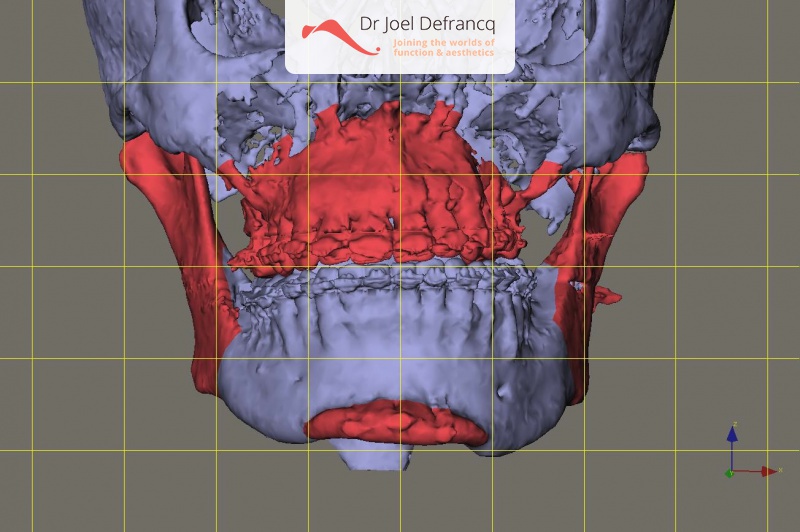

Diagnose van het gezicht

- Te korte bovenkaak

Kaakchirurgie

- Verlenging onderkaak (BSSO)

- Verlenging bovenkaak (Le Fort I)

- Vertikale verlenging bovenkaak (Le Fort I)

- Kinchirurgie

- Redo